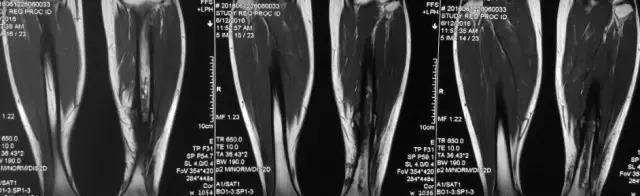

影像检查

诊断:感染。 检查:膝关节MRI,确认伤口窦道是否与髓腔相通。 治疗:1、血沉和C反应蛋白正常,目前无需特殊处理。 2、如果窦道反复出现或血沉和C反应蛋白升高可考虑手术。如证明窦道与髓腔相通,需行扩髓。

核磁示中下段骨髓炎,上面切口处流脓,请问张主任你的意见要上手术吗?

1、是具备手术指征了!也就是说可以手术。 2、并不是必须马上手术。不发热,不红肿、化验都正常也可以换药口服抗生素。